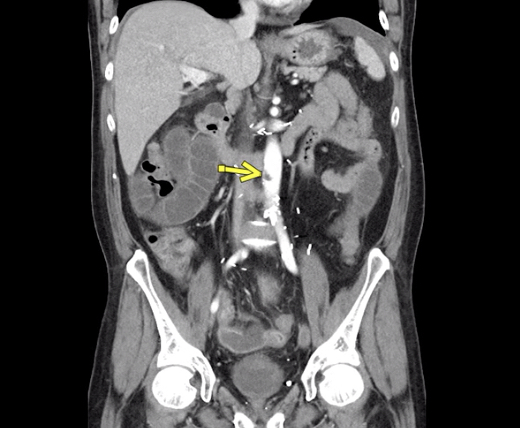

This photo gallery shows the variety of radiological presentations of COVID-19 (SARS-CoV-2) in medical imaging, including computed tomography (CT), radiograph X-rays, ultrasound, echocardiograms and magnetic resonance imaging (MRI). The radiology images show examples of typical COVID pneumonia in the lungs and the numerous complications the virus causes in the body in multiple organs, including the brain, kidneys, heart, abdomen and vascular system.